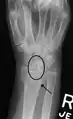

Static scapholunate dissociation